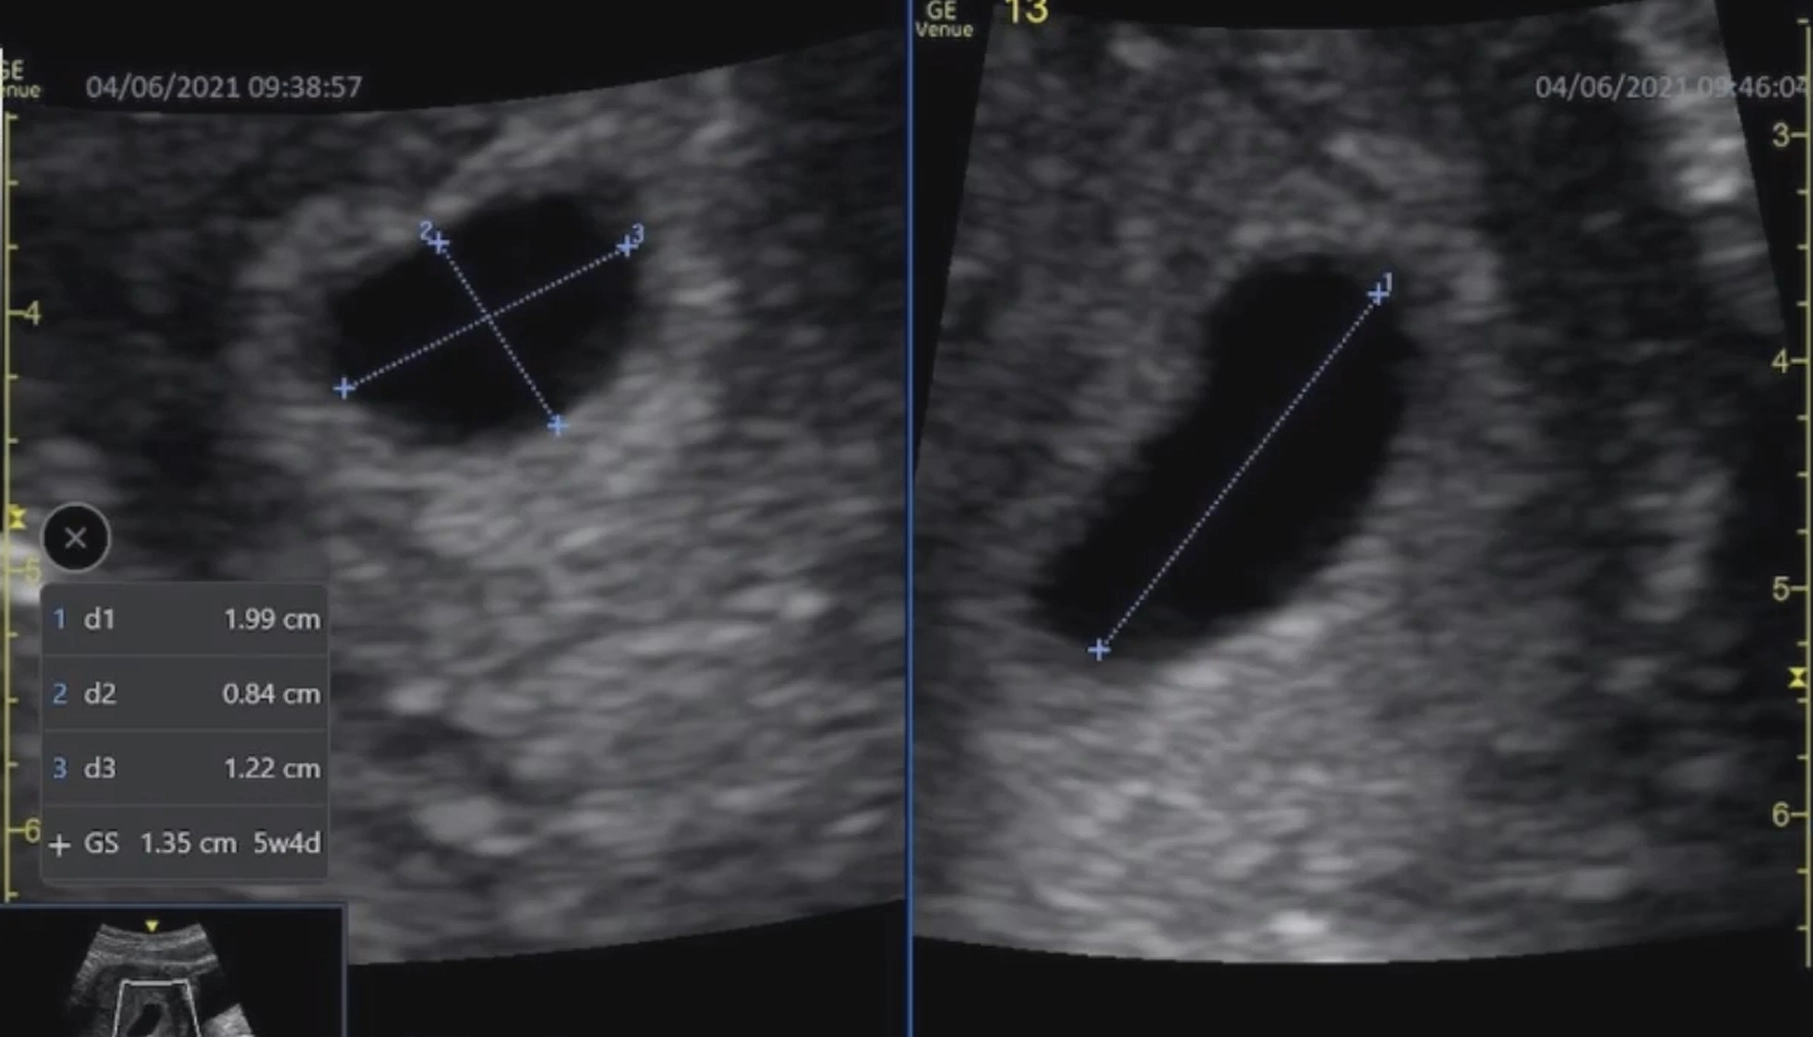

Chỉ số MSD

• Chỉ số MSD